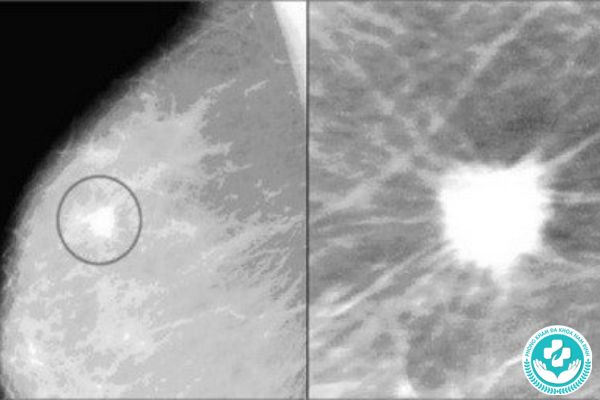

Vôi hóa vú là hiện tượng canxi tích tụ, phát triển trong mô vú, không gây đau và rất nhỏ nên không thể sờ thấy. Vì vậy, người bệnh có thể không biết mình có sang thương vôi hóa trừ khi chụp nhũ ảnh (X-quang tuyến vú).

Vôi hóa thường vô hại nhưng có thể là dấu hiệu sớm của các tế bào bất thường đang phát triển trong mô vú. Kích thước, hình dạng và sự phân bố của vôi hóa có thể là dấu hiệu của tình trạng lành tính hoặc cần xét nghiệm thêm để loại trừ bệnh ác tính.

Vôi hóa tuyến vú thường không gây triệu chứng, kích thước quá nhỏ nên không thể cảm nhận khi khám vú. Người bệnh chỉ có thể biết mình có vôi hóa khi chụp nhũ ảnh định kỳ.

Chẩn đoán bệnh vôi hóa vú

Hầu hết vôi hóa vú đều lành tính và không cần theo dõi đặc biệt. Tuy nhiên, trong một số trường hợp, tình trạng này có thể là dấu hiệu bất thường của tuyến vú. Ví dụ, nếu kết quả chụp nhũ ảnh cho thấy cụm vôi hóa dày đặc hoặc những đốm trắng nhỏ trên 1 đường, bác sĩ sẽ đề nghị xét nghiệm bổ sung để loại trừ ung thư. Các xét nghiệm gồm: